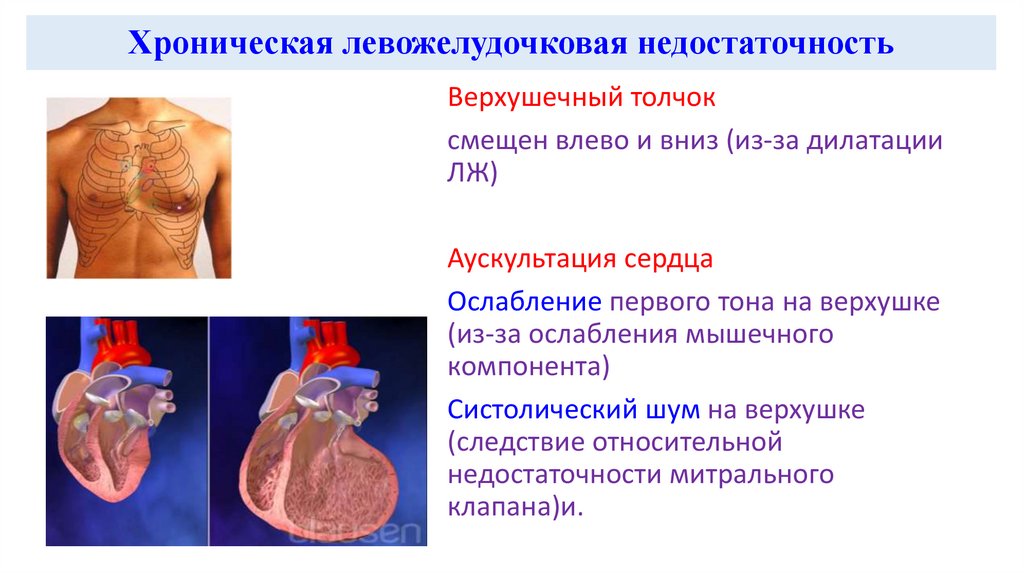

Пороки сердечно-сосудистой системы: виды и признаки